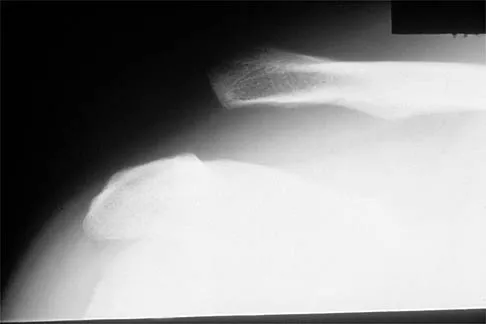

Figure 6a shows the radiograph of a 50-year-old man who sustained an anterior dislocation of the shoulder. He undergoes closed reduction, and the postreduction radiograph is shown in Figure 6b. Management should now consist of

Explanation